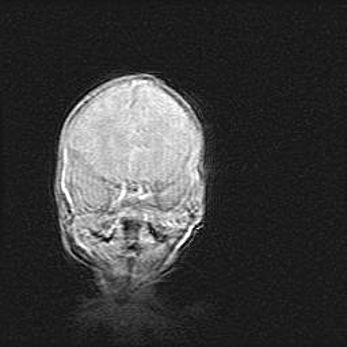

Церебральная ишемия II.

Возраст: 5 дней

Вес: 3400 г

Пол: женский

Окружность головы: 35 см

Срок гестации: 39 недель

Церебральная ишемия – это заболевание, характеризующееся недостаточностью (гипоксией) либо полным прекращением (аноксией) снабжения мозга кислородом по причине закупорки одного или нескольких сосудов. Это приводит к  что метаболическим расстройствам различной степени тяжести в тканях головного мозга, развитию коагуляционных некрозов и гибели нейронов.